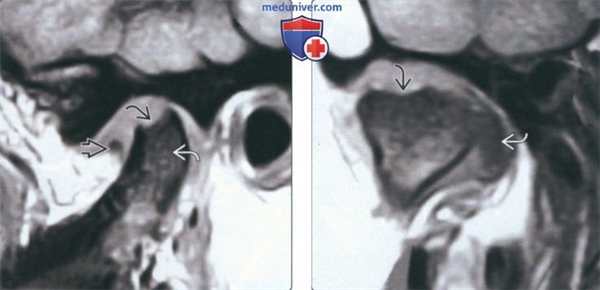

(Слева) На косой сагиттальной MPT (Т1 ВИ) ВНЧС с закрытым ртом не определяется гипоинтенсивный «ободок». В субхондральной кости формируется полость. В костном мозге определяется гипоинтенсивный сигнал (Т1). Мелкий фрагмент дискавизуализируется спереди от мыщелка, остальные отделы диска находятся вне плоскости среза. Эти изменения свидетельствуют об активной фазе дегенеративного заболевания сустава (ДЗС) и сопутствующем отеке костного мозга.

(Справа) На косой корональной MPT (Т1 ВИ) у этого же пациента формируется полость в верхних отделах мыщелка. Диск смещен кпереди и кнутри.